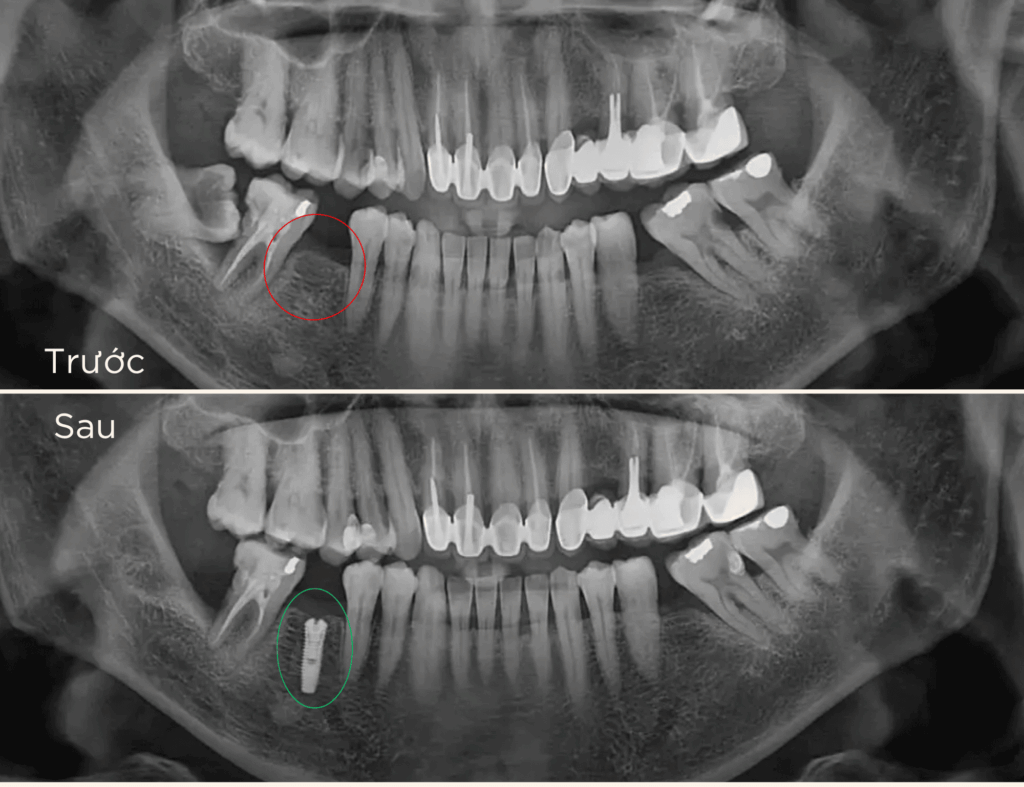

là phương pháp phục hồi răng mất tiên tiến, sử dụng trụ chụ chân răng nhân tạo – Implant từ titanium cấy vào xương hàm để thay thế chân răng đã mất. Sau đó, một mão răng sứ được gắn lên trụ, tạo ra chiếc răng mới với hình dáng và chức năng giống như răng thật.